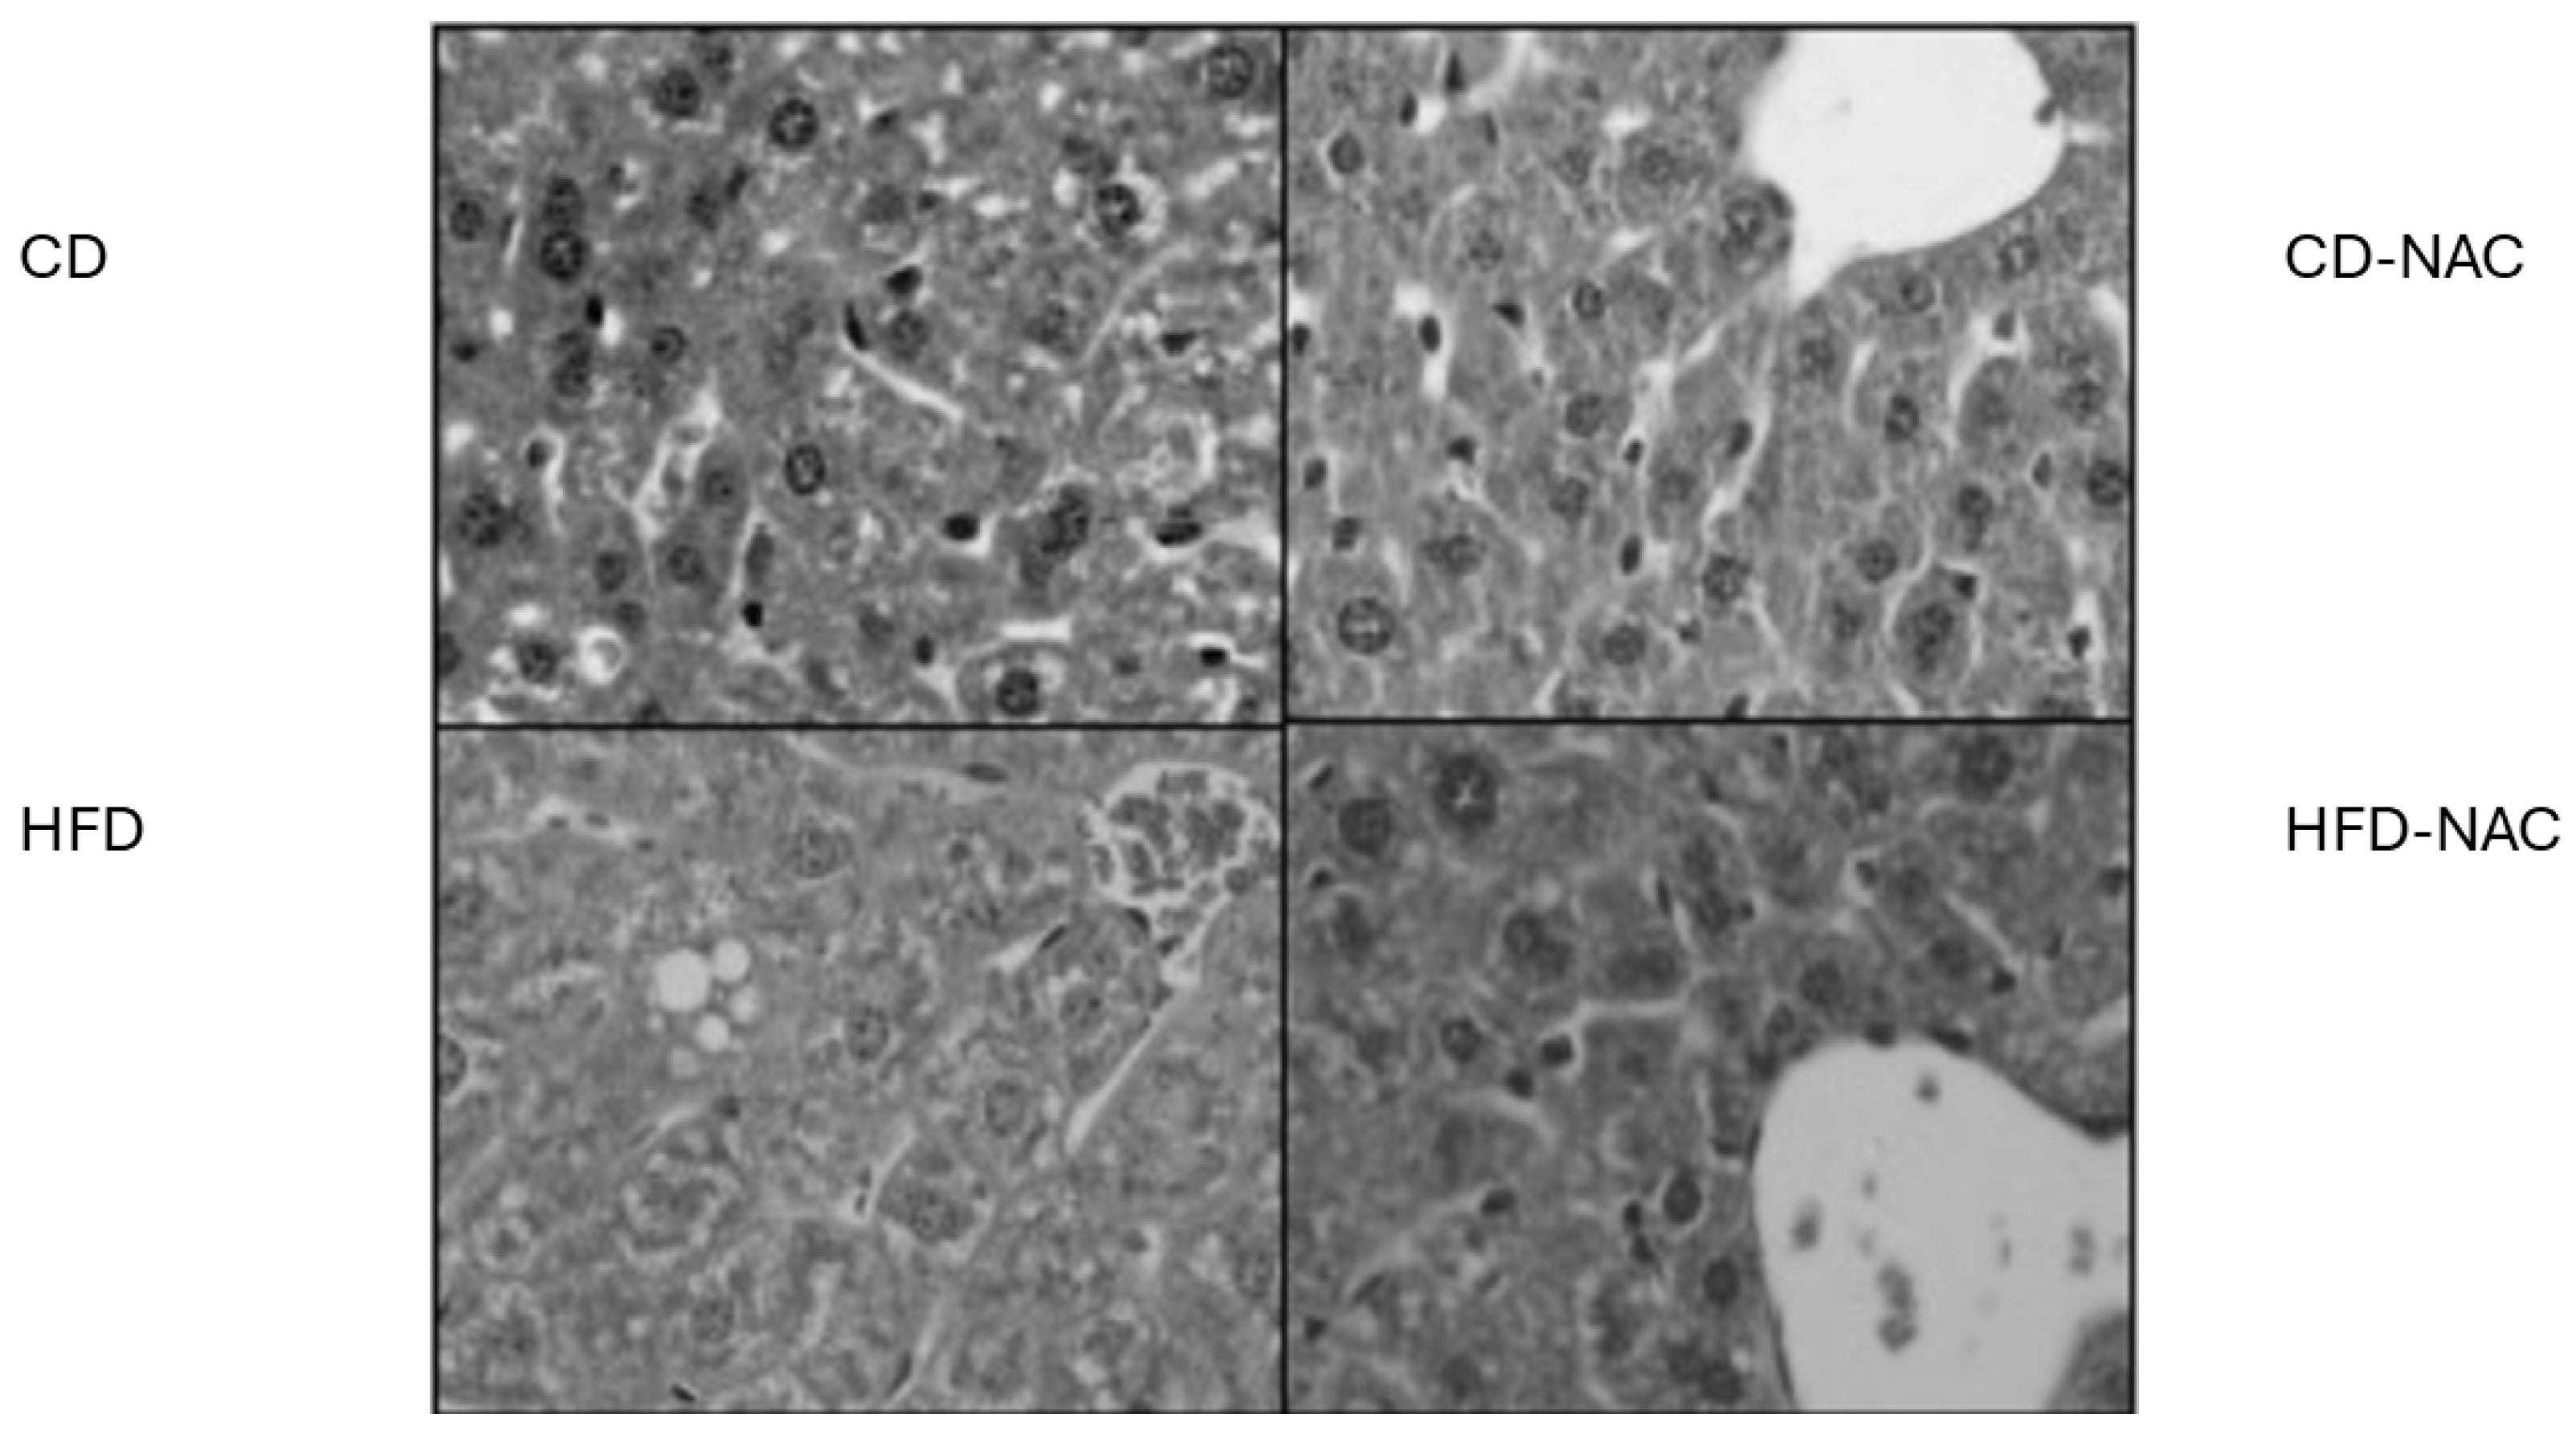

4.7. Histological Analysis